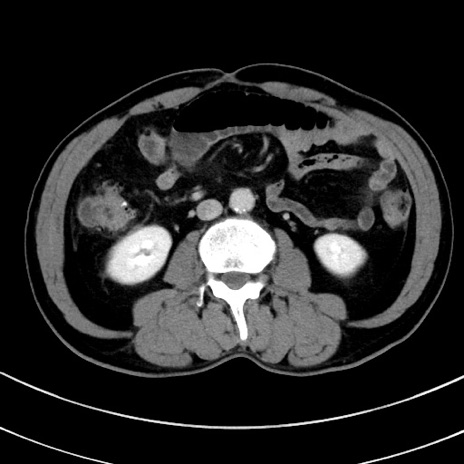

症例8(横断像)

【症例】 60歳代男性

【主訴】 黒色吐物

【現病歴】 4日前から嘔気自覚、2日前の朝食後にも嘔気あり、自分で手で嘔吐反射起こし嘔吐したところ血が混ざっていたため受診。

【既往歴】 5年前汎発性腹膜炎を伴う急性虫垂炎で手術、高血圧、前立腺肥大症、高脂血症

【身体所見】 腹部正中に手術癩痕あり 腹部平坦・軟圧痛なし膨満感あり

【データ】WBC 8400、CRP 4.54